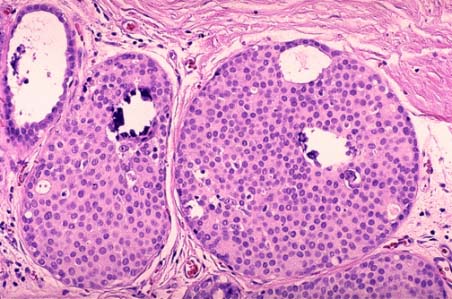

Fig. 2. Carcinom intraductal (aspect microscopic).

DCIS - Carcinomul ductal in situ. Este cancerul mamar detectat cel mai devreme (prima faza), stadiul 0. Se limiteaza la ducte. Toate femeile cu cancer in acest stadiu se pot vindeca. Cea mai buna metoda pentru a depista DCIS este mamografia.